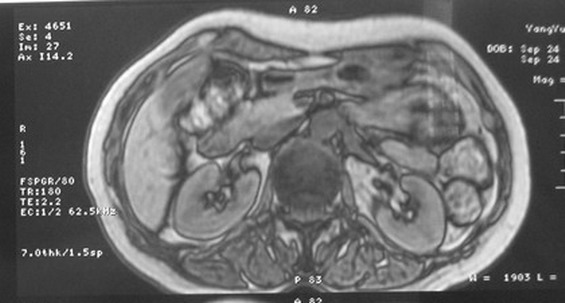

标题: MRI2066:腹膜后占位,请会诊,CT18531近期扫描图像

无明显不适,体检发现,

mri基本排除血管类肿瘤,明显强化说明极富血供,临床无症状,考虑胰岛细胞瘤可能大。

强化明显,并见有血管与之相连;考虑巨淋巴增生症.

极富血供的占位性病变,首先考虑良性,期待结果。